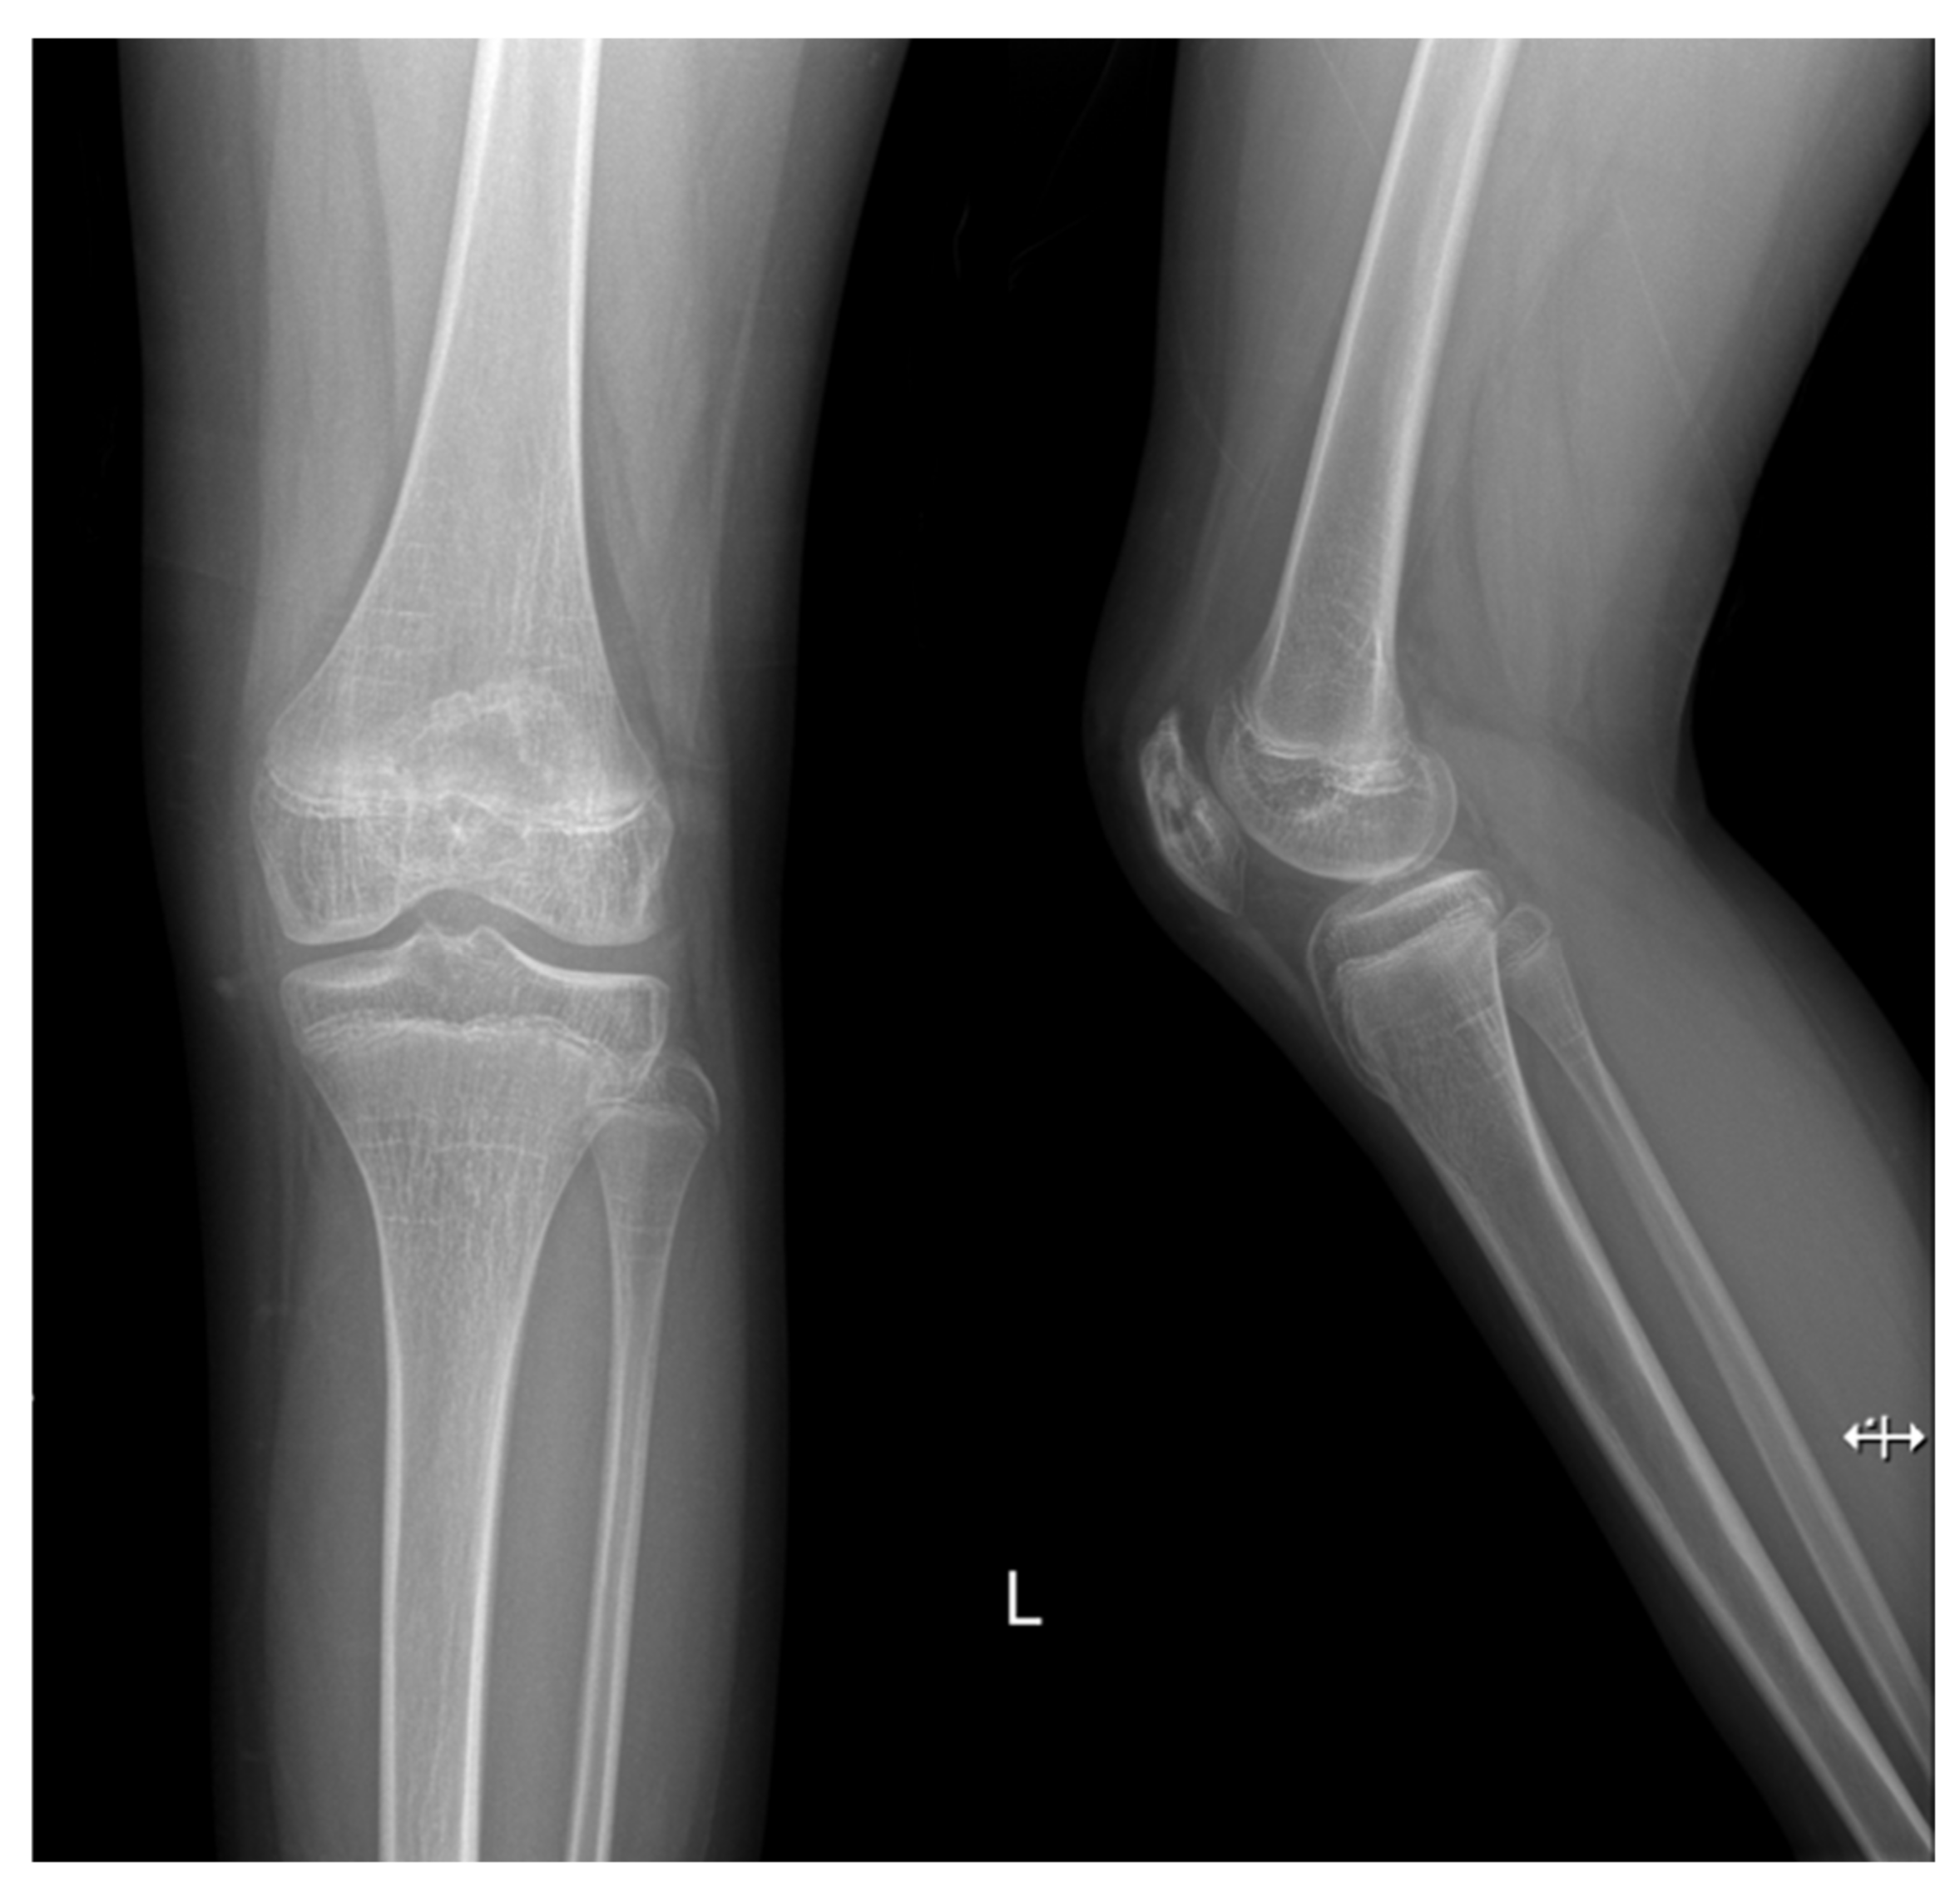

Patellar Osteomyelitis in a 9-Year-Old Patient with Chronic Granulomatous Disease: A Case Report

2. Case Report